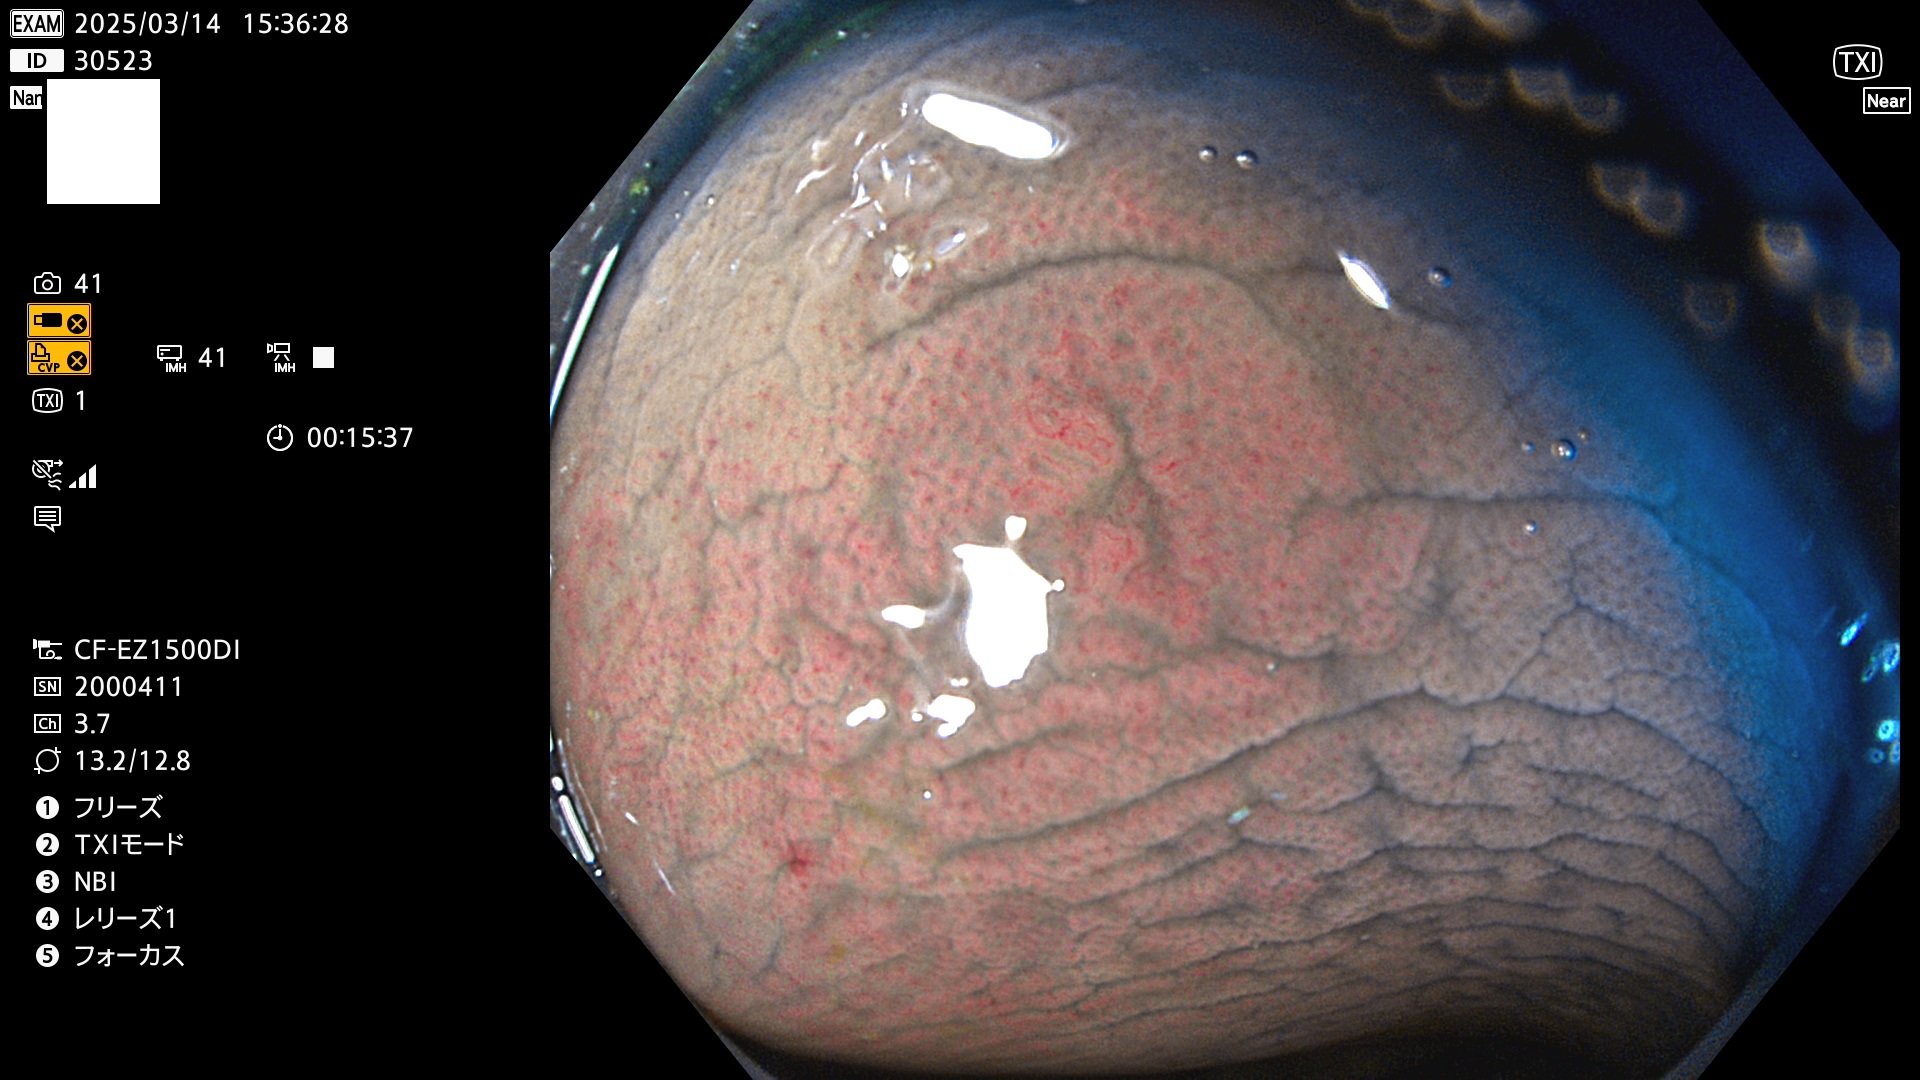

今週のUb、Uc型腺腫

完全に平坦な物をUb、陥凹している物をUcと呼びます。最も発見が難しく危険な病変です。

毎週の検査(木・金・土・日)に発見されたUb、Uc型・腺腫を、その週の日曜の夜にUPし1週間、提示します。

抽出の対象期間 2025年3月13日〜3月16日の4日間(48件の検査)12個 (12/48=25%)